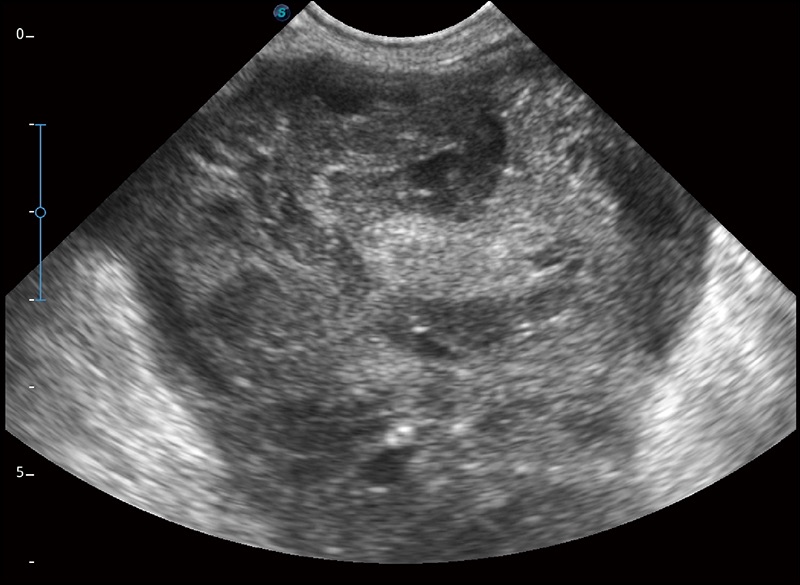

α1卓越的图像质量和便捷的工作流程,使每位宠物医生都能轻松扫查。其全面的兽用应用功能和紧凑型的结构设计,可以满足动物检查的多种需要。专业的预设检查模式和多领域测量软件包有助于为不同类型的动物提供检查, 让宠物医生能够出色的完成工作。

穿刺针增强

高清显示穿刺进针情况